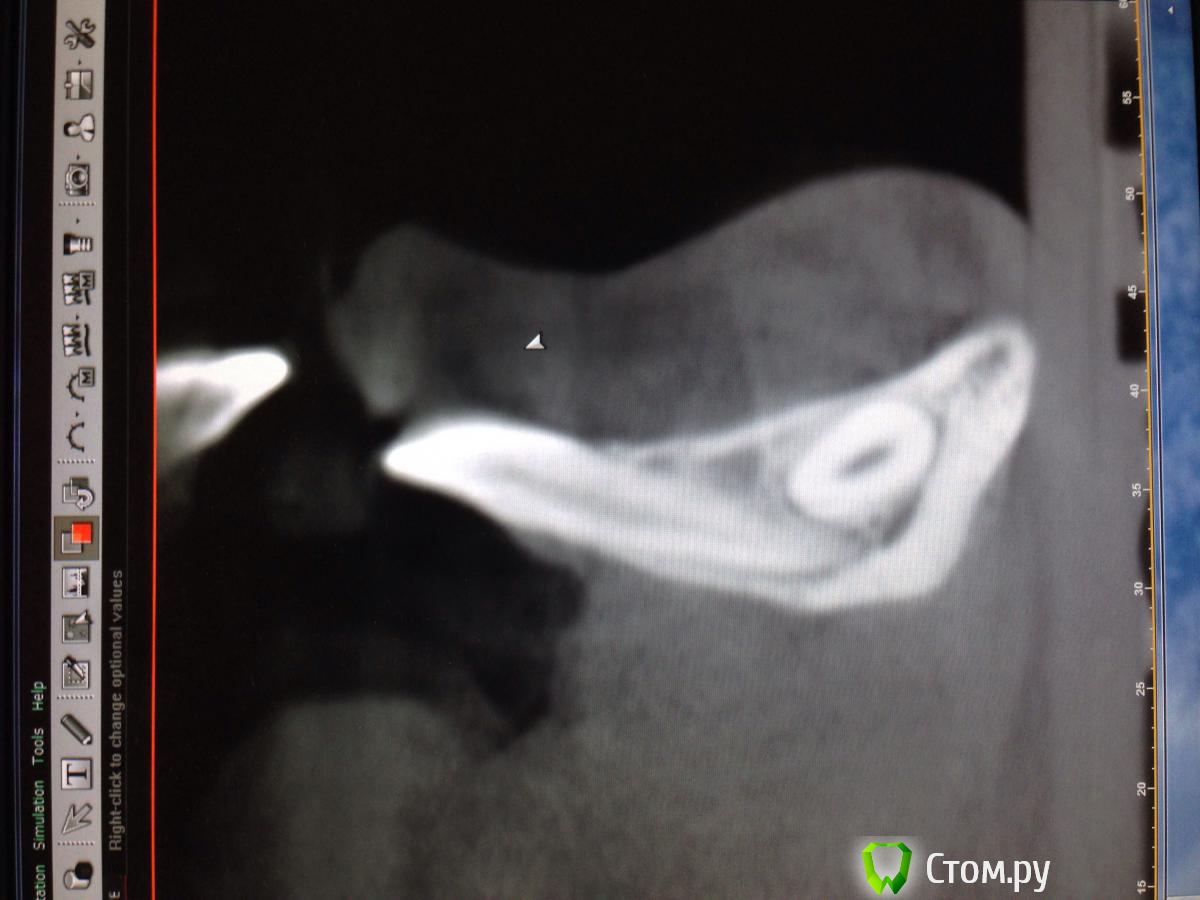

Opimar Опубликовано 29 ноября, 2013 Поделиться Опубликовано 29 ноября, 2013 Прошу совета по тактике лечения. Ортодонты привели пациента, 43 надо удалять. Впринципе ничего такого я не вижу, но все-таки как грамотно поступить взяться амбулаторно или направить в стационар. План лечения: Внутрибороздковый пошире с отслойкой передней поверхности подбородка ну и бор машиной фрагментировать зуб и удалить, либо без фрагментации если так пойдет. Швы, антибиотики, холод. Ну и предупредить о возможном онемении и травме резцов. Ссылка на комментарий

Alexey Doc Опубликовано 29 ноября, 2013 Поделиться Опубликовано 29 ноября, 2013 Амбулаторное удаление.Вот только дизайн разреза нужно првильный выбрать!не думаю что втутрибороздковый разрез создаст условия для оптимального доступа, да и отслойка при нем будет на большой площади. я бы сделал линейный ниже уровня переходной складки , если он не будет проходить над планируемым костным дефектом. 3 Ссылка на комментарий

kriokov Опубликовано 29 ноября, 2013 Поделиться Опубликовано 29 ноября, 2013 Разрез послойный:сперва слизистую в области переходной, затем мышцы (ушивание в обратной последовательности). Отверстие на уровне (приблизительно) средины корня. Три сегмента.Удаляете средний, дальше по ситуации.В дефект-от коллагена до графта.Давящая повязка снаружи.если доктор не делал низких доступов, трудно будет сообразить по первой как ушиться. Может уж чуть выше разрез сделать по нижней границе прикрепленной если прикрепленной хватает? И риск рецессии меньше чем при сулькулярном, и одним блоком надкостницу с мышцами поднимет, и ушьется почаще но в один слой, и ветки ментального в мягких тканях если чего целые будут.? 3 Ссылка на комментарий